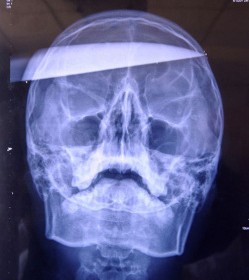

Une bagarre a alors éclaté dans l'établissement et l’un des assaillants du présumé tricheur a planté un couteau rouillé dans la tête de l’adolescent. La victime a eu le crâne transpercé d’un bout à l’autre comme le montre la photographie ci-dessus.

La victime a été transportée d'urgence à l’hôpital et a subi une opération chirurgicale afin d'extraire le couteau du crâne.

La victime a survécu car le couteau n’a touché aucune artère, et n’a pas affecté des endroits du cerveau qui régulent le fonctionnement moteur du corps. Les probabilités de survivre à ce genre de blessure est d'une sur un millier d'après les médecins.